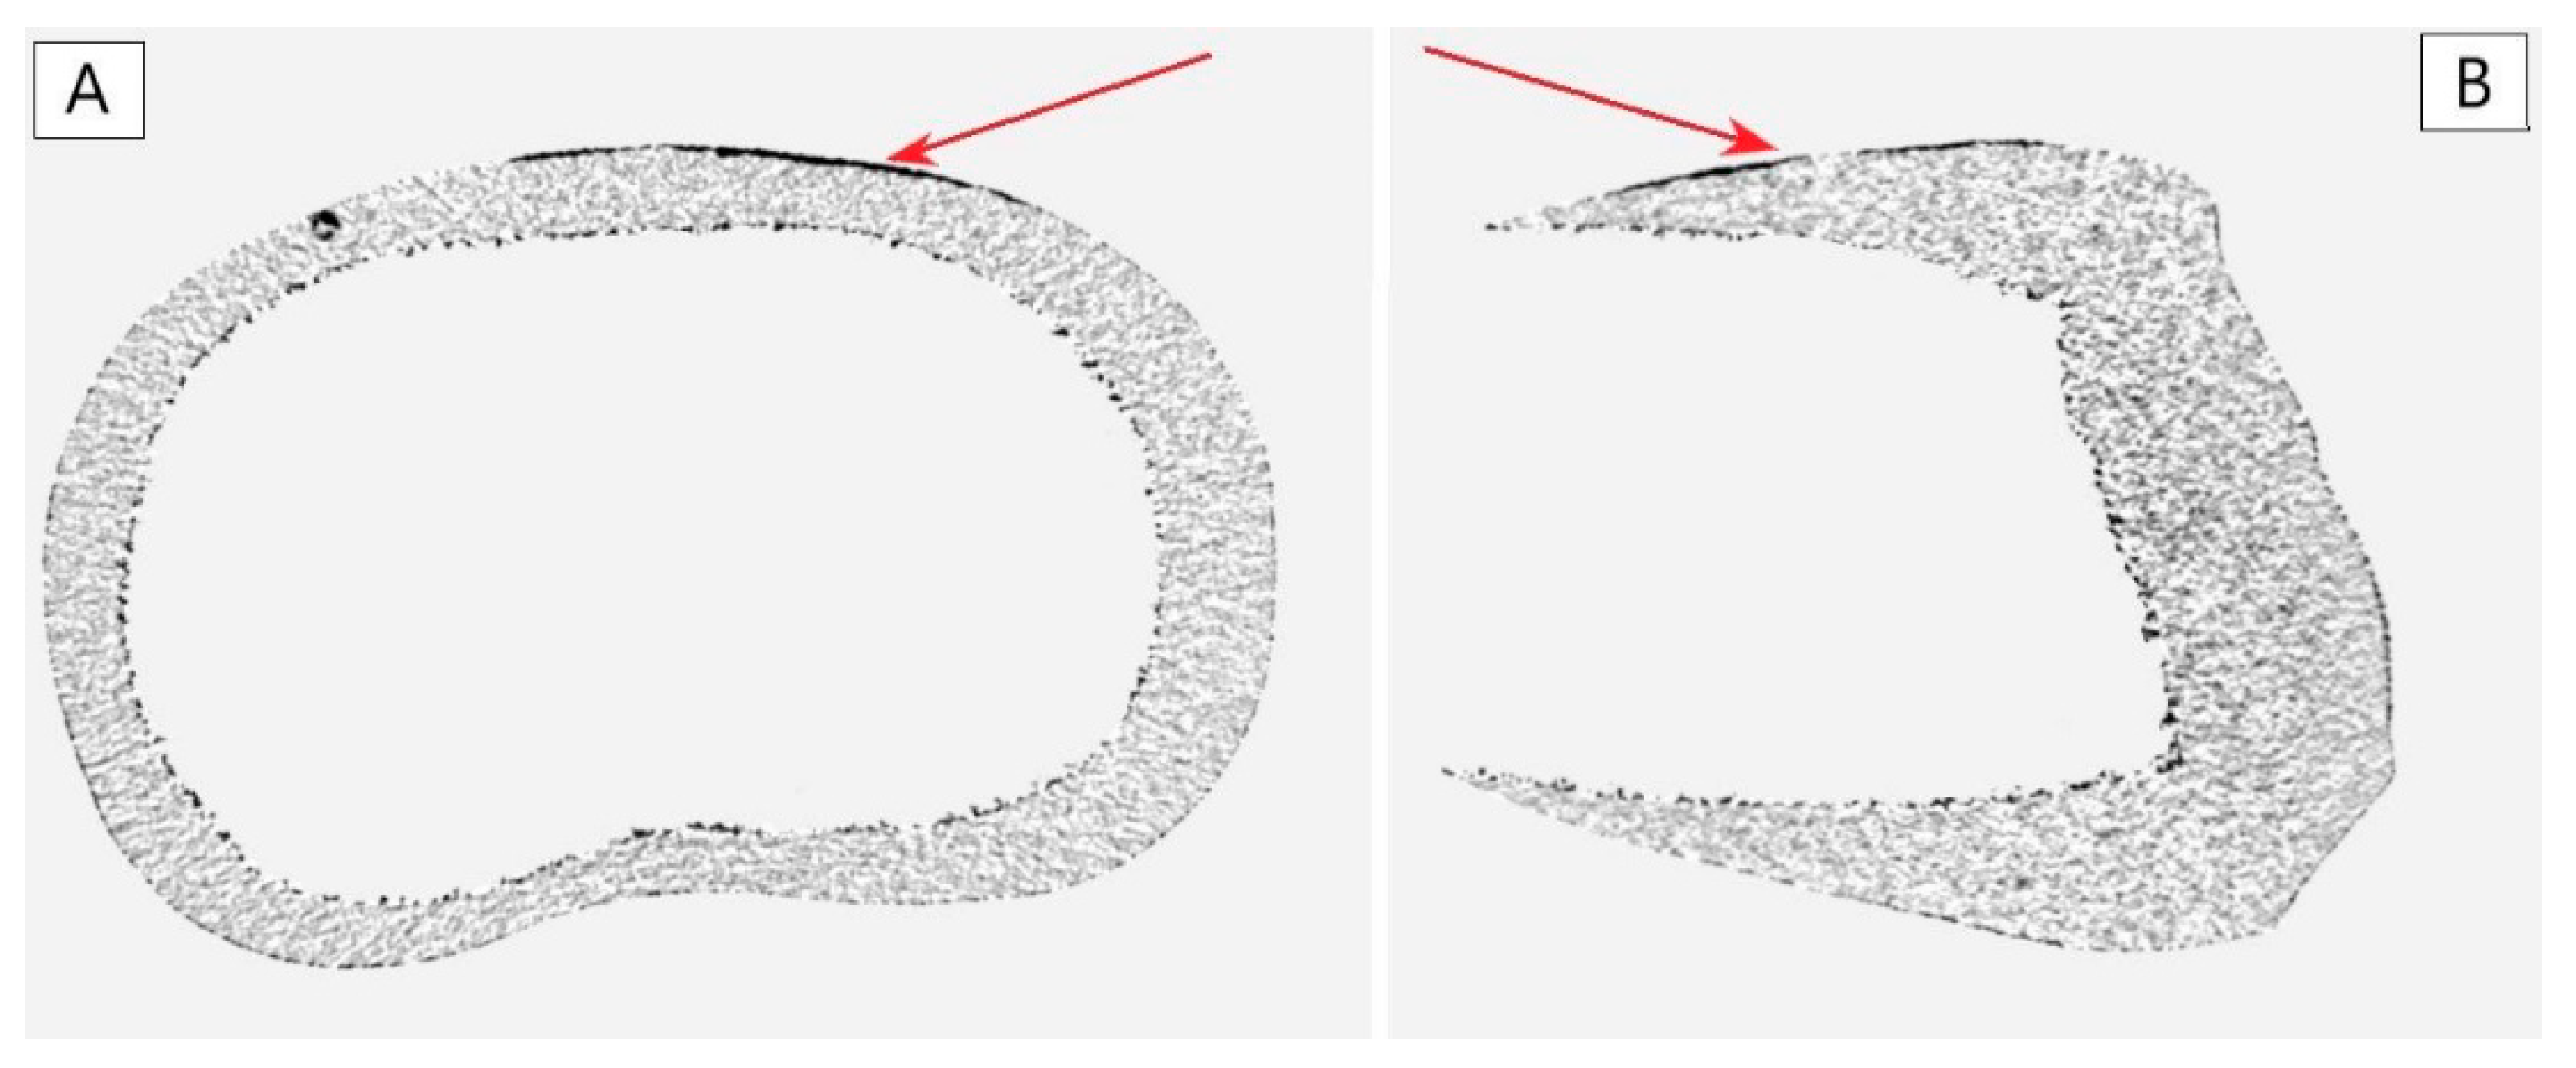

3.3. The Analysis of the Enamel Surface, Prepared by Different Conditioning Techniques